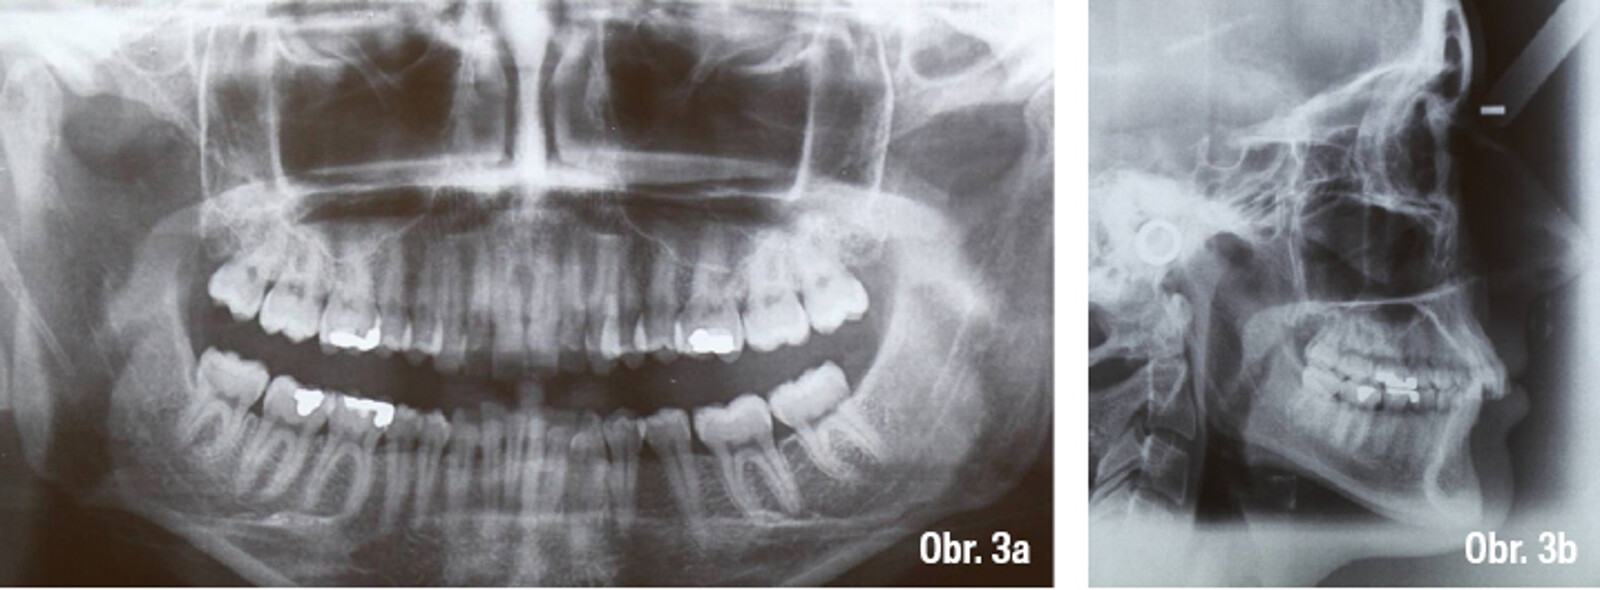

Lingvální zámky 3M™ Incognito™ System a kombinovaná ortodontickochirurgická terapie